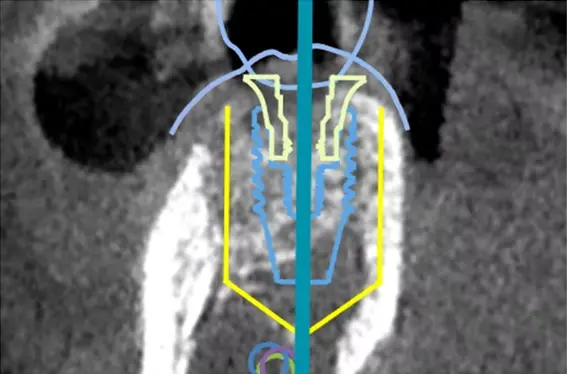

Xガイドは、歯や骨の状態に加え、神経や血管の位置を含めた3D画像を手術中にリアルタイムで表示し、インプラントの埋入位置と角度を正確にナビゲートするシステムです。

このシステムでは、赤外線カメラを用いた光学式トラッキング技術により、ドリルの位置、角度、深さをリアルタイムで画面に表示します。これにより、術前に立てたCTベースの治療計画と、実際の手術操作を常に照合しながら治療を進めることができます。

ナビゲーションシステム(Xガイド)の画像